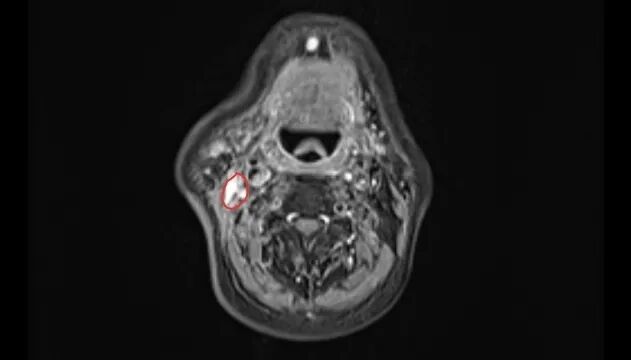

结果证实了张大伯的担忧:其右腮腺区及颈部有一个约4厘米×4厘米的肿大淋巴结,经穿刺活检确诊为鼻咽癌转移。

完成两个周期治疗后,影像复查显示,他颈部的转移淋巴结已明显缩小。目前,张大伯仍在继续接受治疗,他的脸上也重现了笑容:“多亏了毛主任和团队,让我又看到了希望。”